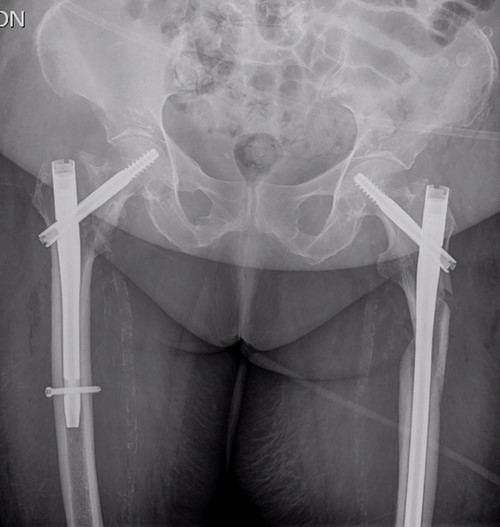

The postoperative course was satisfactory, without medical problems apart from non-complicated anemia (Hb 7.9 g/dl), solved with two units of red blood. On the first postoperative day, a radiographic control was completed (Fig. 3) and started early ambulation assisted by physiotherapists. On day twelve, she was transferred to a rehabilitation hospital. Outpatient follow-up visits evolving reasonably well. In the 6-month and 1-year check-up, the consolidation of the fracture was observed in the radiographic study (Fig. 4). No surgical wound problems, infections, or limping were identified. Anti-osteoporotic drug treatment was implemented along with an emphasis on a healthy diet with adequate protein intake and supplementation with calcium and vitamin D.

Radiological evaluation on follow-up at 1 year. Pelvis anteroposterior radiograph view showing signs of consolidation, without evidence of loss of reduction or implant failure.